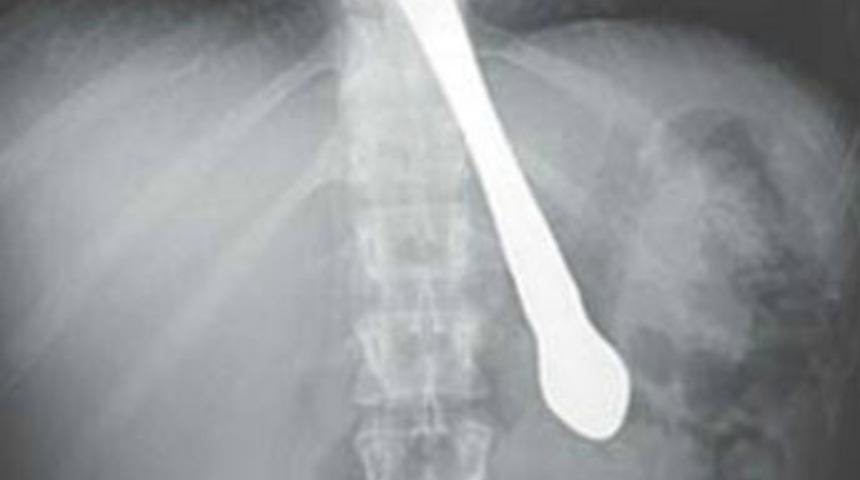

ABD'de 30 yaşındaki bir kadın arkadaşlarını eğlendirmek için ağzına koyduğu bıçağı, yapılan bir espriye gülünce yanlışlıkla yuttu.

ABD’nin Georgia eyaletinin başkenti Atlanta’da yaşayan bir kadın arkadaşlarına hiçbir şeyin midesini bulandırmadığını kanıtlamak için tereyağı bıçağını ağzına koydu. Yapılan bir espriye gülen kadın yarısı boğazına kadar inmiş olan bıçağı yuttu.

Talihsiz kazanın ardından kusmaya başlayan kadın vakit kaybetmeden hastaneye kaldırıldı. New York Daily News gazetesinin haberinde göre midesınden operasyon geçiren kadının sağlık durumunun iyi olduğu bildirildi.